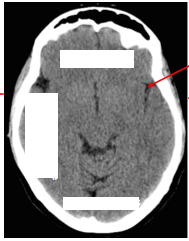

T2 weighted MRI:

What is the appearance of bone?

What is the appearance of CSF?

On a T2 weighted MRI bone will appear black and CSF will appear white.

Note also that cerebral grey matter can be distinguished from white matter tracts on a T2 weighted MRI.

Label image

What are the arrows pointing to on the image?

What two important structures are shown in the image?